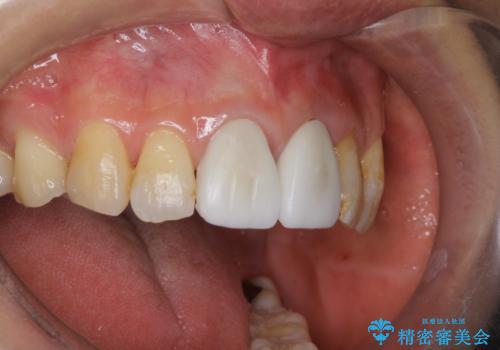

前歯については、上顎の前歯8本(右上4321、左上1234)の治療を希望されたため、右上32、左上23番目の歯は虫歯及び樹脂の除去後、オールセラミッククラウン(スタンダード)による補綴を行いました。

痛みのあった右上1、及び歯の神経が死んでいた左上4番目の歯は根管治療を行い、ファイバーコアによる築造後、オールセラミッククラウン(スタンダード)による補綴を行いました。

右上4及び左上1番目の歯は再根管治療を希望されなかったため、ファイバーコアによる築造後、オールセラミッククラウン(スタンダード)による補綴を行いました。

今回用いたオールセラミッククラウンはジルコニアフレームという白い素材の上にセラミックを盛っているため、審美性が非常に高いのが特徴です。

また、ジルコニアは人工ダイヤモンドの材料にも使われているほど高い強度を持っており、そのためオールセラミッククラウンは審美性だけでなく、奥歯やブリッジの補綴も可能とするクラウンです。